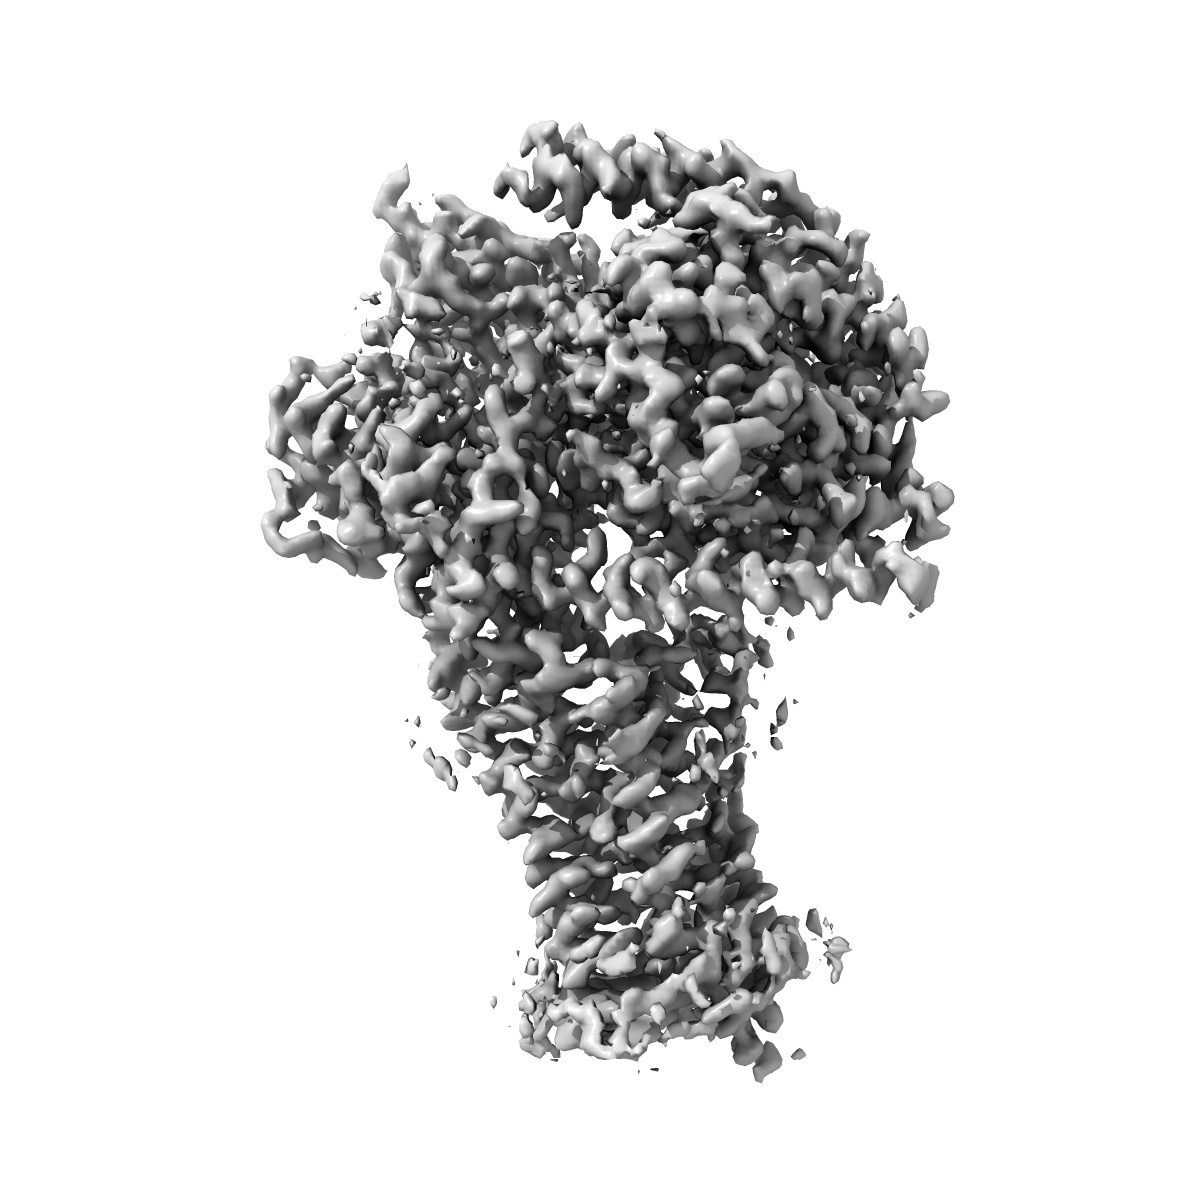

Human Cholecystokinin 1 receptor (CCK1R) Gs complex

Sample: CCK1R/CCK-8/Gas complex

Structures of the human cholecystokinin 1 (CCK1) receptor bound to Gs and Gq mimetic proteins provide insight into mechanisms of G protein selectivity.